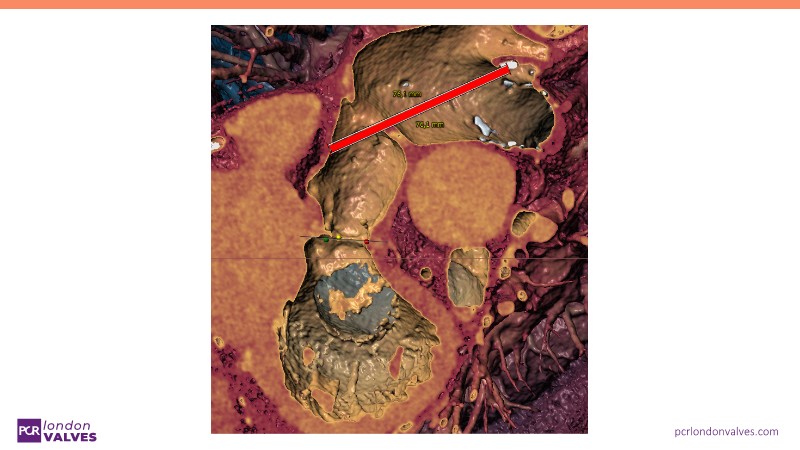

This session offers an in-depth review of complex TAVI cases, focusing on overcoming clinical challenges and achieving optimal outcomes with the Evolut FX+ device. Participants will learn about recent advances in TAVI indications for younger and asymptomatic patients, strategies for managing TAV in surgical aortic valve (SAV) patients including redo TAVI, and explore technological innovations designed to address complex anatomical scenarios.

- To discern the latest technological evolutions that enable the treatment of patients with complex anatomy